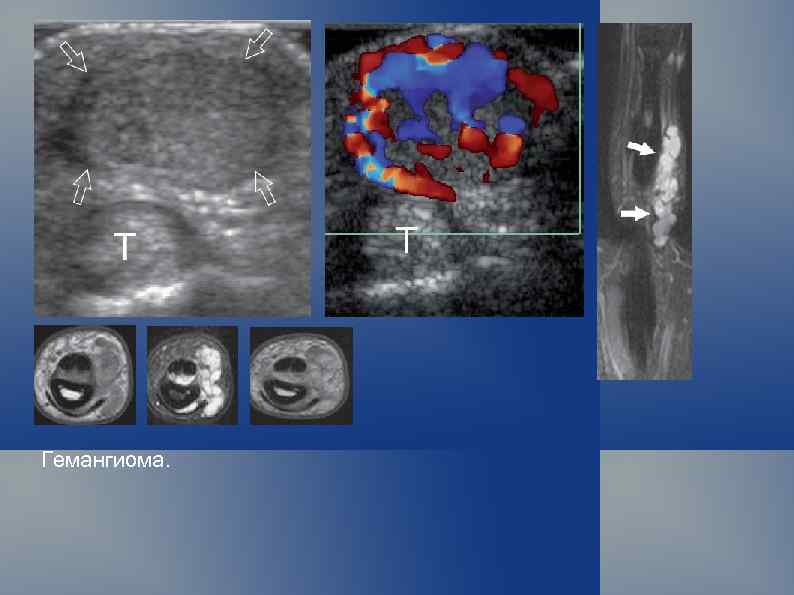

Гемангиома.